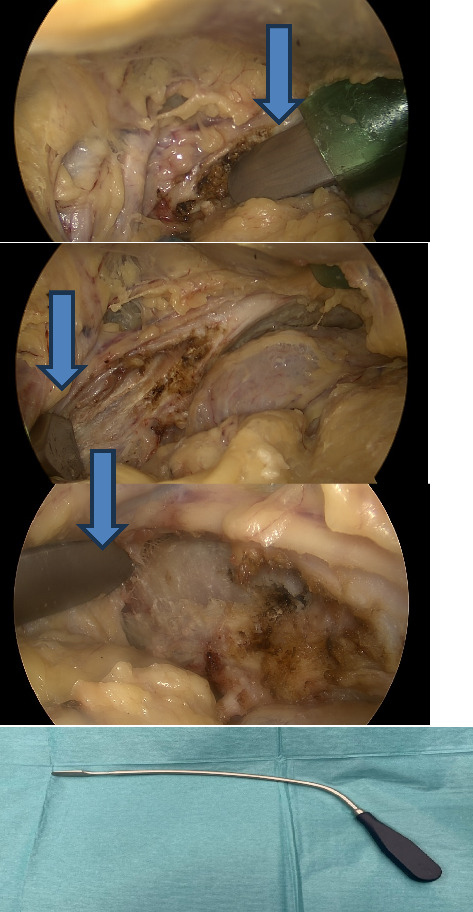

背景和目的:在传统开放手术中对髋臼骨折进行操作时,关键结构的可视化可能具有挑战性。近年来,已有多篇关于腹腔镜辅助髋臼手术的病例报道。因此,我们利用腹膜外内窥镜进一步发展了这种方法来处理髋臼骨折。手术方法手术技术:由经验丰富、熟悉腹膜外腹腔镜技术的疝气外科医生协助进入髋臼区域,以便骨科医生通过腹腔镜端口用钢板和螺钉集中固定该区域。结果:我们在尸体实验室中开发了这种手术技术,在腹膜外内窥镜的可视化下,我们可以轻松地对七具尸体的左右两侧髋臼区域进行固定和钢板安装。结论:髋臼骨折的全内窥镜微创手术与传统的开放手术相比,具有康复快、失血少、伤口并发症少等显著优势。根据我们在尸体上获得的初步经验,与开放手术相比,这种微创方法具有更好的可视性,更容易进入骨盆区域原本狭窄且难以进入的骨折部位。此外,这种微创方法在内窥镜和荧光透视的联合可视控制下精确放置钢板似乎是可行的。这种新方法在现实生活中微创治疗髋臼骨折的实用性,特别是考虑到适当的骨折复位的实用性,应在未来的临床试验中得到证实。

Background and Objectives: When operating on acetabular fractures in conventional open surgery, visualization of crucial structures can be challenging. In recent years there have been several case reports on laparoscopy-assisted acetabulum surgery in the literature. Therefore, we have developed this method further using extraperitoneal endoscopy to manage acetabulum fractures. Methods: Operative technique: An experienced hernia surgeon familiar with the totally extraperitoneal laparoscopic technique facilitates access to the acetabulum area so that orthopaedic surgeons can focus on fixing the area with a plate and screws through laparoscopy ports. Results: We developed this operative technique in a cadaver laboratory where we could easily fix and plate the acetabulum area with extraperitoneal endoscopy visualization in seven cadavers both on the left and right sides. Conclusions: A minimally invasive full endoscopic procedure for acetabular fractures offers significant benefits over traditional open surgery due to faster rehabilitation, potentially less blood loss, and fewer wound complications. According to our initial experiences with cadavers, this minimally invasive method appears promising in terms of superior visibility and easier access to the otherwise narrow and difficult fracture site in the pelvic region compared to open surgery. Furthermore, this minimally invasive method seems feasible for exact plate placement under combined endoscopic and fluoroscopic visual control. The usefulness of this novel method in the minimally invasive treatment of acetabular fractures in real life, especially considering the practicality of proper fracture reduction, should be confirmed in future clinical trials.